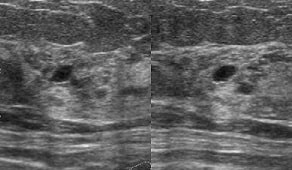

<乳癌の症状>

乳房のしこり、隆起、陥凹。乳汁分泌、血性乳汁。